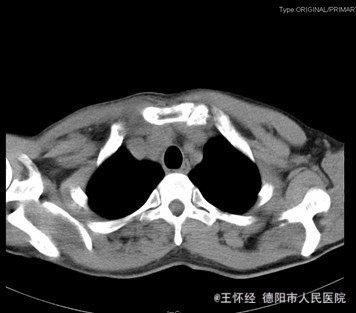

查体:右侧胸锁关节处叩压痛明显,可扪及一隆起、质硬,右侧胸壁乳头周围肿胀,右肩外展因胸锁关节处疼痛而受限受限。 辅查:X片及CT提示示右侧胸锁关节向前脱位、双侧第一肋骨骨折

初步诊断:车祸伤:1.右侧胸锁关节前脱位;2.双侧第一肋骨骨折。 诊疗计划:右侧胸锁关节脱位切开复位,锚定固定修复关节囊及周围韧带。

术中见右侧胸锁关节处可见软组织突起,可扪及活动的锁骨远端。皮下软组织挫伤、水肿,胸锁乳突肌止点完整。胸锁关节前脱位,胸锁关节囊、关节软骨盘撕裂。